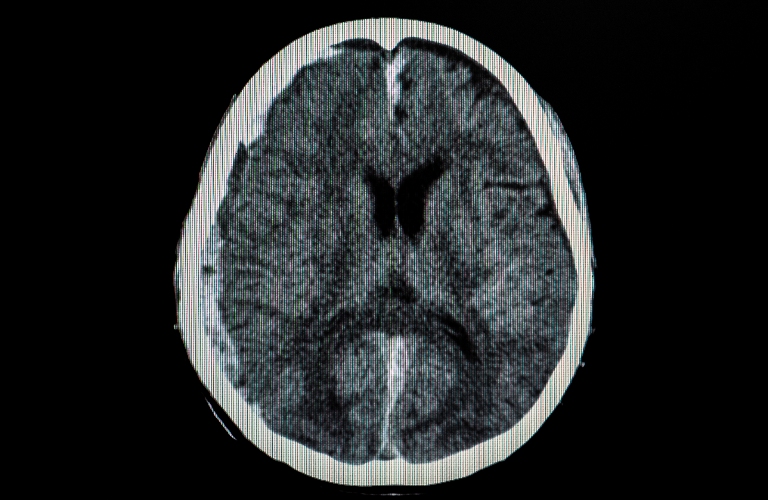

What Is a Traumatic Brain Injury?

A traumatic brain injury (TBI) occurs when a sudden injury causes damage to the brain. TBIs can range from mild, commonly known as concussion, to severe, potentially leading to long-term cognitive, emotional, and physical impairments. According to the U.S. Department of Veterans Affairs, more than 450,000 service members have been diagnosed with a TBI since 2000, many linked directly to combat and training-related incidents.